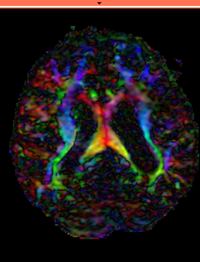

Slicer Registration Library Exampe #3: Diffusion Weighted Image Volume: align with structural reference MRI

This is a typical example of DTI processing. Goal is to align the DTI image with a structural scan that provides accuracte anatomical reference. The DTI contains acquisition-related distortion and insufficient contrast to discern anatomical detail.

MRI, brain, head, intra-subject, DTI, DWI

• Button red fixed white.jpgreference/fixed : T2w FSE,

• Button green moving white.jpg moving: Baseline image of acquired DTI volume, corresponds to T2w MRI , 0.9375 x 0.9375 x 1.4 mm voxel size, oblique

• 20px moving: Tensor data of DTI volume, oblique, same orientation as Baseline image. The result Xform will be applied to this volume.